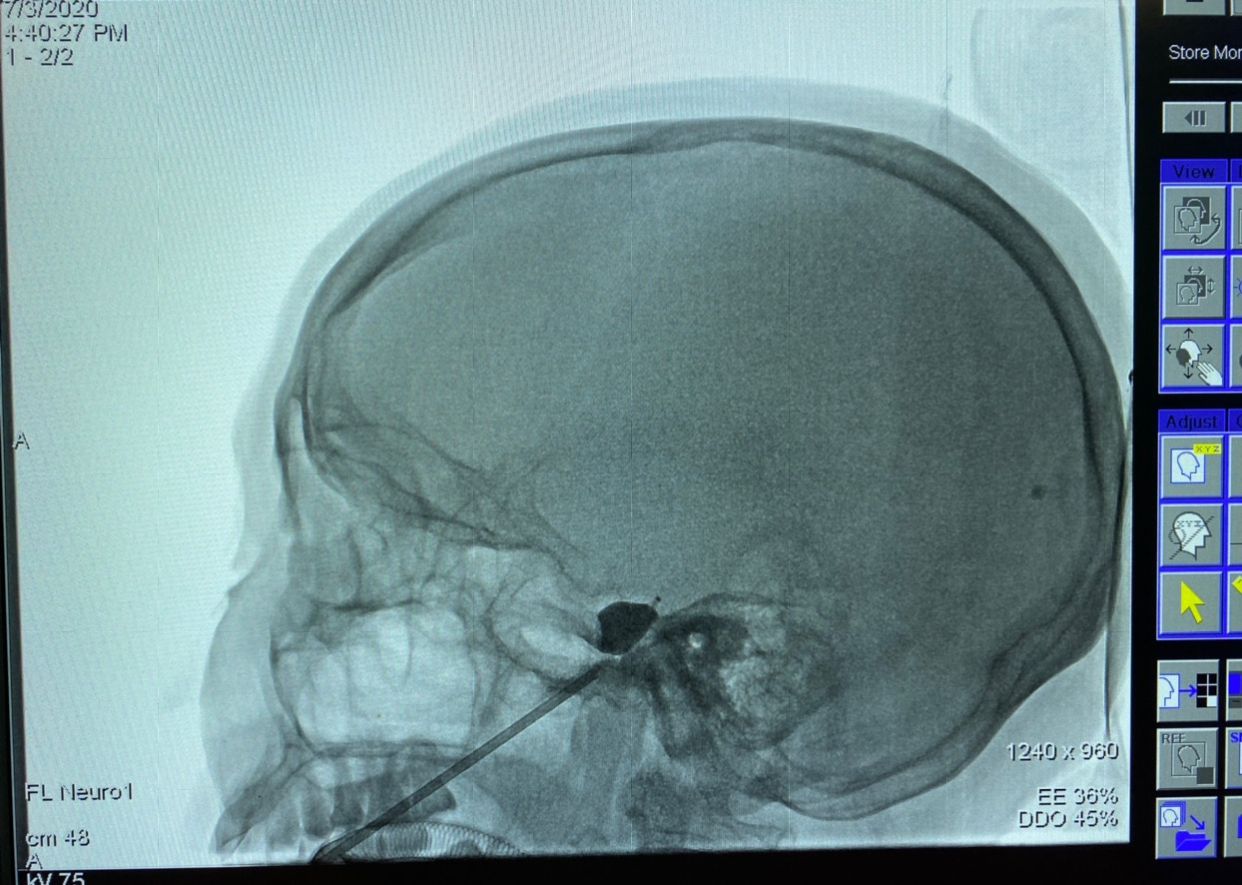

如果正常三叉神经痛患者,术中显示该球囊,术后效果疼痛缓解没问题,但该患者累及右侧头皮疼痛,所以,球囊导管需要再次调整。